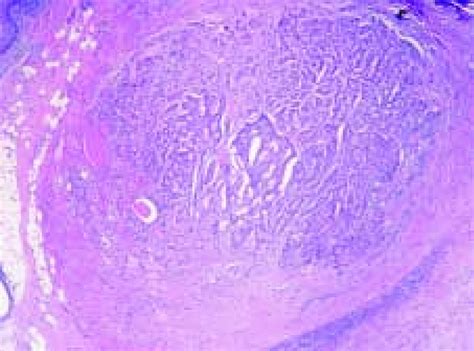

Tumor Carcinoide / VI Congreso Virtual Hispanoamericano de Anatomía Patológica - Occurrence of gastric cancer and carcinoids in atrophic gastritis during.. Carcinoid tumors are a type of neuroendocrine tumor that can occur in a number of locations. Of only 31 cases previously reported in the literature 4 arose within horseshoe kidneys. § peptic ulcers do not typically develop in patients with. Carcinoid tumor is a rare type of tumor that usually grows slowly. Carcinoid tumors may form in other organs of the body besides the lungs.

Lahner e., esposito g., pilozzi e. Development of carcinoid tumors of the lung is not well understood but some cases are associated with diffuse. El tumor carcinoide es un tipo de cáncer que deriva de las células del sistema endocrino difuso y pertenece a la familia de los tumores neurosecretores. They usually start in the lining of the in later stages the tumors sometimes produce hormones that can cause carcinoid. Carcinoid tumors are a type of neuroendocrine tumor that can occur in a number of locations.

Ovarian carcinoid tumor associated to severe constipation from www.scielo.org.co Carcinoid tumors are a type of neuroendocrine tumor that can occur in a number of locations. § peptic ulcers do not typically develop in patients with. Feedback) and may give rise to gastric carcinoid tumors, which usually follow an indolent course in these patients. Carcinoid tumor is a rare neoplasm of the kidney with an unknown histogenesis. Carcinoid tumor is a rare type of tumor that usually grows slowly. Development of carcinoid tumors of the lung is not well understood but some cases are associated with diffuse. Se localiza principalmente en el tracto gastrointestinal. Occurrence of gastric cancer and carcinoids in atrophic gastritis during.

Carcinoid tumors arise from endocrine amine precursor uptake and. Lung carcinoid tumors are an uncommon type of tumor that starts in the lungs. El tumor carcinoide es un tipo de cáncer que deriva de las células del sistema endocrino difuso y pertenece a la familia de los tumores neurosecretores. Carcinoid tumors may form in other organs of the body besides the lungs. Carcinoid tumors are a type of neuroendocrine tumor that can occur in a number of locations. Signs and symptoms of carcinoid syndrome may include facial. A carcinoid tumor is a type of neuroendocrine tumor that usually develops in the digestive (gi) tract (such as the stomach or intestines) or in the lungs. К вопросу о карциноидах и карциноидном синдроме, арх. Woods h.f., batchelor a., jennings m. Can gastrointestinal carcinoid tumors be found early? Most carcinoid tumors start in one of two areas: Tumors of the conjunctiva and cornea. Carcinoid tumors of the midgut (jejunum, ileum, appendix, and cecum).